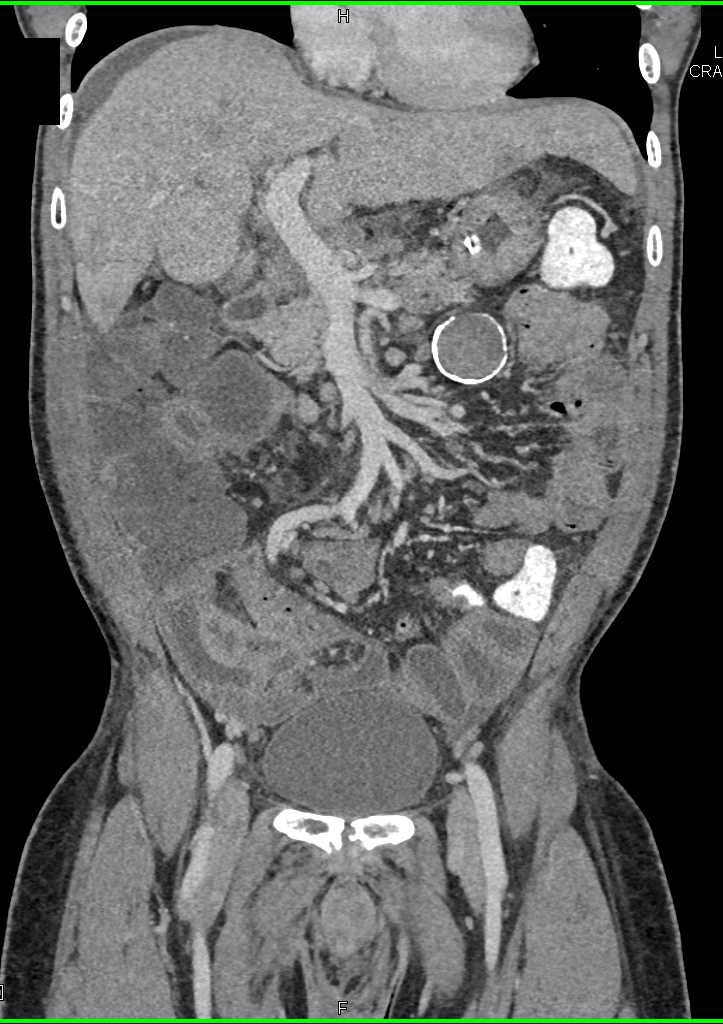

Small Bowel Carcinoma with Carcinomatosis